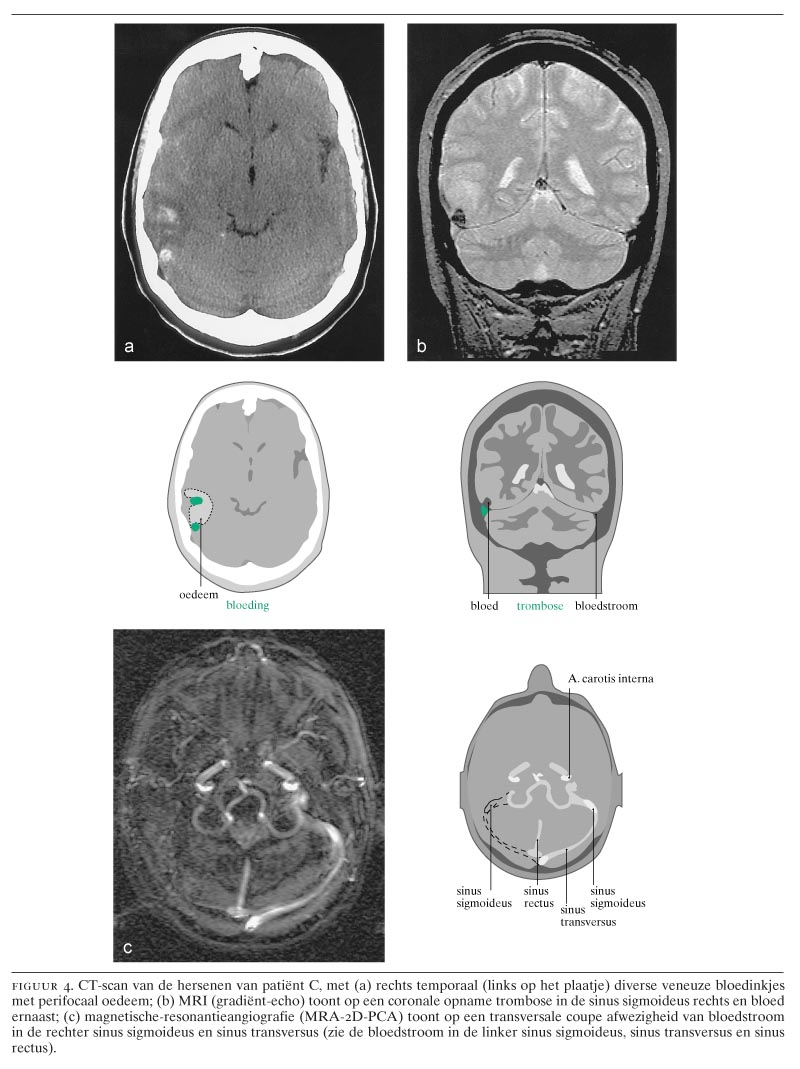

Acute Hevige Hoofdpijn Subarachnoidale Bloeding Nederlands Tijdschrift Voor Geneeskunde